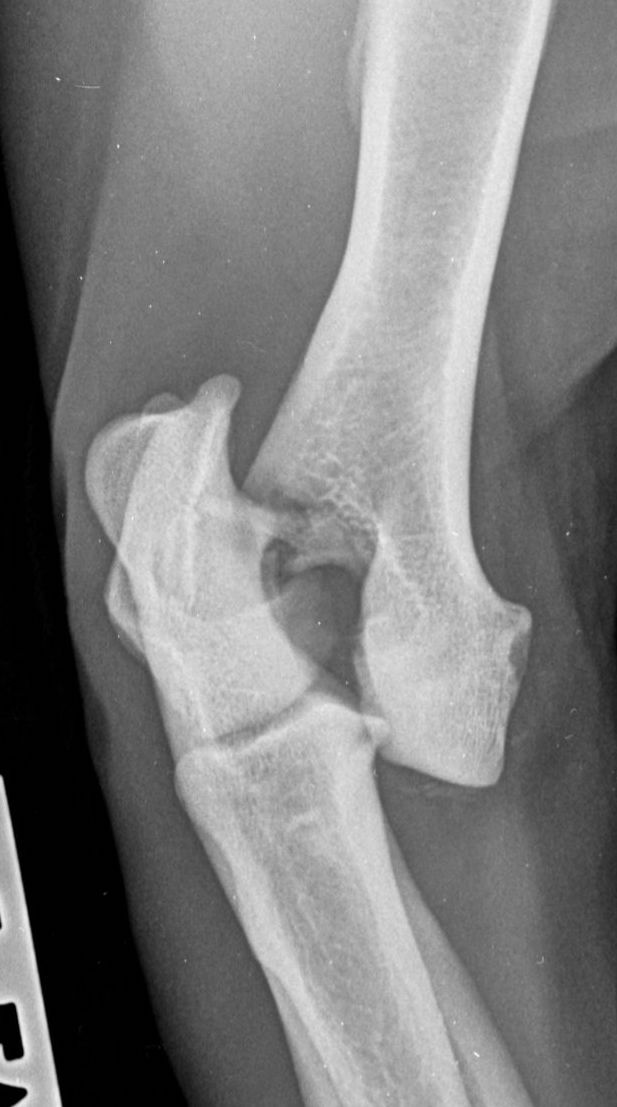

Traditionally, humeral unicondylar (lateral or medial) fractures have been managed with internal fixation using a transcondylar bone screw and an anti-rotational device. This is generally a Kirschner wire (K-wire) or Steinmann pin (Figure 1), which is placed across the epicondylar ridge component of the fracture (Bojrab, 1975; Denny and Butterworth, 2000; Jackson, 1983; Olmstead, 1993). However, reports of complications relating to mechanical failure due to implant migration in a series of patients varying widely in age and breed concluded that using a supracondylar K-wire is more likely to cause major complications than using an epicondylar bone plate (Perry et al., 2015; Sanchez Villamil et al., 2019). This conclusion was endorsed by an in vitro study that showed that stiffness, yield load and load to failure are all greater when bone plates, rather than K-wires, are used in conjunction with a transcondylar bone screw to stabilise humeral unicondylar fractures (Coggleshall et al., 2017).

These concerns have led to recommendations being altered over the past decade or so, with veterinarians now using bone plates, instead of K-wires, as an adjunct to a transcondylar screw when managing humeral unicondylar fractures (Figure 2), even in puppies (Figure 3) (Clark, 2016; Kvale et al., 2022). However, the basis on which this conclusion for puppies was reached appears to have been flawed because it assumed that what had been shown to be the case for adults would also apply to immature patients. As the conclusion was felt to conflict with the author’s experience of treating such patients, a retrospective study was undertaken to evaluate complications and outcomes in immature dogs treated for humeral unicondylar fractures at one centre over a 10-year period (Butterworth, 2022). The findings of this study are summarised in this article.